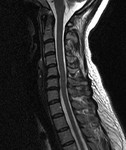

[画像診断]胸椎・腰椎損傷について(外傷)【研修医と学ぶ】 2011-03-29